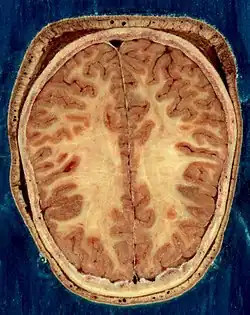

O cérebro, que consiste nos hemisférios cerebrais, forma a maior parte do encéfalo e recobre as outras estruturas cerebrais[6] A região externa dos hemisférios, o córtex cerebral, é a massa cinzenta, consistindo de camadas corticais de neurônios. Cada hemisfério é dividido em quatro lobos principais - o lobo frontal, o lobo parietal, o lobo temporal e o lobo occipital.[7] Três outros lobos são incluídos por algumas fontes, que são um lobo central, um lobo límbico e um lobo insular.[8] O lobo central compreende o giro pré-central e o giro pós-central e está incluído, pois forma um papel funcional distinto.[8][9]

O cérebro, o tronco cerebral, o cerebelo e a medula espinhal são cobertos por três membranas chamadas meninges. As membranas são a dura-máter resistente; a aracnóide e a pia-máter interna, mais delicada. Entre a aracnoide e a pia-máter estão o espaço e as cisternas subaracnoides, que contêm o líquido cefalorraquidiano.[10] A membrana mais externa do córtex cerebral é a membrana basal da pia-máter e é uma parte importante da barreira hematoencefálica.[11] O cérebro vivo é muito macio, tendo uma consistência de gel semelhante ao tofu.[12] As camadas corticais de neurônios constituem grande parte da matéria cinzenta cerebral, enquanto as regiões subcorticais mais profundas dos axônios mielinizados constituem a matéria branca.[6] A substância branca do cérebro representa cerca de metade do volume total do cérebro.[13]

O cérebro é a maior parte do encéfalo e é dividido em hemisférios direito e esquerdo quase simétricos por um sulco profundo, a fissura longitudinal.[14] A assimetria entre os lobos é observada como uma petália.[15] Os hemisférios são conectados por cinco comissuras que abrangem a fissura longitudinal, a maior delas é o corpo caloso.[6] Cada hemisfério é convencionalmente dividido em quatro lobos principais; o lobo frontal, o lobo parietal, o lobo temporal e o lobo occipital, nomeados de acordo com os ossos do crânio que os cobrem.[7] Cada lobo ou lóbulo está associado a uma ou duas funções especializadas, embora haja alguma sobreposição funcional entre elas.[16] A superfície do cérebro é dobrada em cristas (giros) e ranhuras (sulcos), muitos dos quais são nomeados geralmente de acordo com sua posição, como o giro frontal do lobo frontal ou o sulco central, que separa as regiões centrais dos hemisférios. Existem muitas pequenas variações nas dobras secundárias e terciárias.[17]

A parte externa do cérebro é o córtex cerebral, composto de matéria cinzenta organizada em camadas. Tem 2 a 4 milímetros de espessura e é profundamente dobrado para dar uma aparência complicada.[18] Abaixo do córtex está a matéria branca cerebral. A maior parte do córtex cerebral é o neocórtex, que possui seis camadas neuronais. O resto do córtex é de alocórtex, que tem três ou quatro camadas.[19]